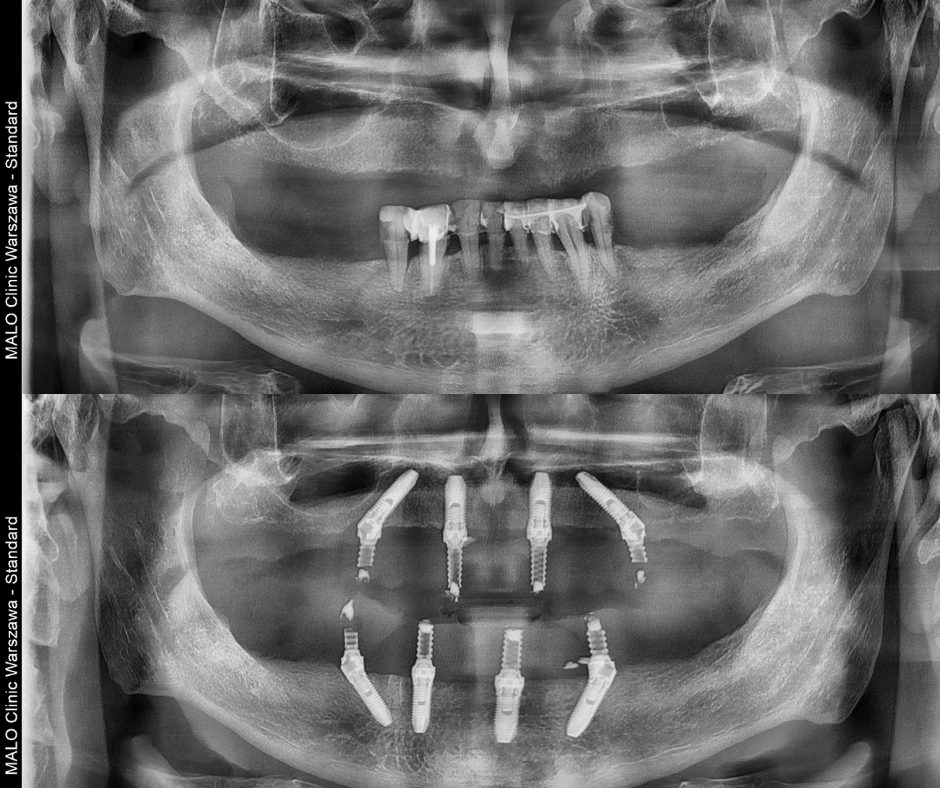

Po rozmowie z rodziną, Pan Mirosław postanowił skonsultować się ze specjalistami w zakresie implantologii. Zgłosił się do Malo Clinic, gdzie został objęty kompleksową diagnostyką i kwalifikacją do leczenia. Po analizie stanu zdrowia i wyników badań, lekarz zaproponował mu leczenie z wykorzystaniem metody Malo Clinic Protocol techniką All-on-4® w górnym i dolnym łuku zębowym.

To nowoczesna metoda leczenia braków uzębienia, opracowana ponad 25 lat temu przez zespół Malo Clinic w Portugalii. Polega na osadzeniu pełnego łuku zębowego na czterech implantach, co umożliwia przywrócenie funkcji żucia, estetyki i komfortu w krótkim czasie – przy spełnieniu odpowiednich warunków medycznych.

- Leczenie obejmuje usunięcie zębów, wszczepienie implantów i tymczasową odbudowę w trakcie jednego dnia zabiegowego – po wcześniejszym dokładnym zaplanowaniu i kwalifikacji.

- zdjęcie panoramiczne (OPG),

- tomografia komputerowa,

W ciągu jednego dnia zabiegowego, po usunięciu zębów (jeśli to konieczne), możliwe jest wszczepienie implantów i osadzenie tymczasowego mostu, który umożliwia mówienie, jedzenie i uśmiechanie się już po kilku dniach.